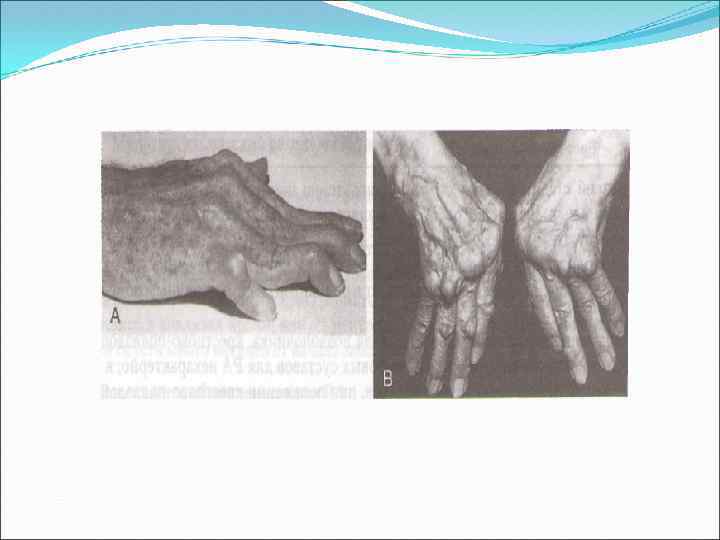

Поражение суставов при РА

Поражение суставов при РА